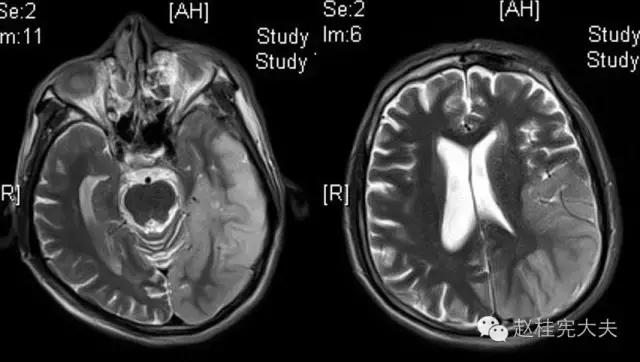

入院前1天的头颅CT:

定位诊断:混合性失语,定位于左侧大脑半球语言中枢(运动和感觉),右侧中枢性面舌瘫,定位于左侧面神经核团以上,右侧上下肢肌力下降,病理征阳性,定位于左侧锥体束。感觉、视野查体无法配合,暂无相应定位考虑。综合考虑,定位于左侧大脑中动脉分布范围。头颅CT:左侧颞叶片状低密度影,左侧大脑中动脉下干支配区,支持临床定位。

定性诊断:结合57岁,男性,急性病程,逐渐加重,进展性右侧肢体无力、混合性失语。头颅CT:左侧颞叶片状低密度影。脑梗死为首先考虑,左侧大脑中动脉支配区,大动脉粥样硬化型。尽管患者本人无高血压、糖尿病等危险因素,但患者母亲有中风、糖尿病史,存在家族中风危险因素,故待完善血生化及血管等卒中危险因素筛查。入院后继续急诊抗血小板、降脂稳定斑块及脑保护治疗。

完善检查,头颅MRI回报:左侧颞顶枕叶急性梗死灶。